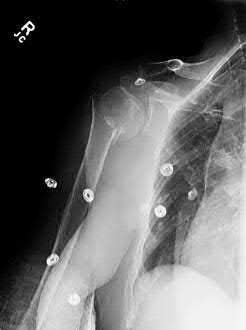

A 68-year-old osteoporotic female sustains a proximal humerus fracture. The AP radiograph is shown. According to the Hertel criteria, which of the following radiographic features is the most reliable predictor of humeral head ischemia?

Options:

- Anatomical neck fracture pattern

- Greater tuberosity displacement > 1 cm

- Metaphyseal head extension (calcar segment) less than 8 mm

- Varus angulation greater than 20 degrees

- Disruption of the medial periosteal hinge > 2 mm

Correct Answer: Metaphyseal head extension (calcar segment) less than 8 mm

Explanation:

Hertel et al. described radiographic criteria predictive of humeral head ischemia. The most reliable predictors include a metaphyseal head extension (calcar segment) of less than 8 mm, disruption of the medial hinge (>2 mm), and an anatomic neck fracture. Among the choices, the calcar segment length < 8 mm represents a highly predictive sign that the primary blood supply (the ascending branch of the anterior humeral circumflex artery and intraosseous vessels) has been severely compromised.